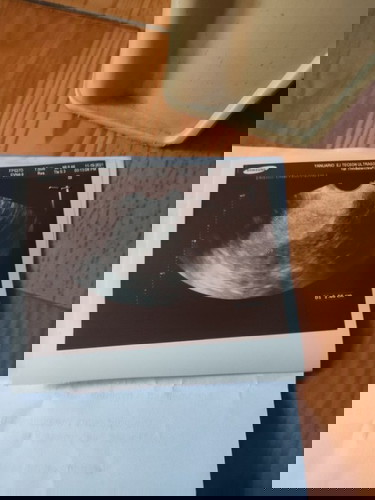

No embryo? Normal ba?

Base sa lmp ko 7weeks na ko buntis pero walang baby normal po ba un ??? First time mom ko po nasakit din puson ko#1stimemom

Kahit sac wala nakita? Ako nag pa trans v ako sa lpm ko 6 weeks tas MSD ko 5 weeks according sa sac size. sac lang nakita wala pa baby after 2 weeks balik ako hopefully makita na baby ko., pray lang po.

ako po nag pa OB wala dn pong nkitang baby sakin 😥last period ko dec 28, tpos nag pt po ako positive nmn sya dalawa then nag pa ultra ako after 8weeks walang nakitang baby 😥

saken ganyan din. walang laman na baby pero may inunan. naging anembryonic pregnancy. nakunan ako.